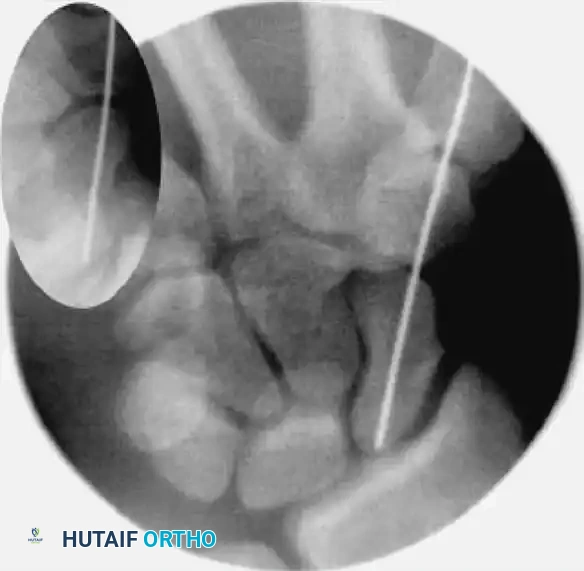

FIGURE: Percutaneous fixation of scaphoid fracture. (A) Central axis of scaphoid located on PA view. (B) Wrist pronated until poles align. (C) Wrist flexed until the scaphoid demonstrates the classic "ring" appearance, indicating coaxial alignment.

1. Fluoroscopic Targeting and The "Ring Sign"

The cornerstone of the Slade percutaneous dorsal approach is achieving the correct fluoroscopic view to target the central axis of the scaphoid.

• Achieving the Ring Sign: Gently pronate and flex the patient's wrist. Because the scaphoid sits obliquely, flexing and pronating the wrist aligns the proximal and distal poles coaxially with the fluoroscopy beam.

• When perfectly aligned, the scaphoid will project a cortical "ring" appearance on the fluoroscopic monitor. The exact center of this "ring" represents the central axis of the scaphoid—the optimal starting point for the guidewire.